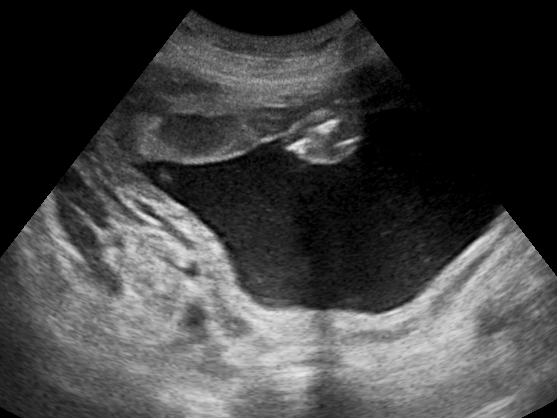

양수 과다증은 임신 중 양수가 과도하게 축적되는 상태를 의미하며, 정확한 원인을 알 수 없는 경우가 많다. 원인으로는 산모의 당뇨병, 심장 및 신장 질환, 태아의 기형, 다태 임신, 태아 부속물의 이상 등이 있으며, 특히 태아의 위장관 폐쇄, 신경학적 이상, 염색체 이상 등이 관련될 수 있다. 증상으로는 산모의 복부 팽만, 호흡 곤란, 태동 감소 등이 나타나고, 태아는 조산, 저체중아, 선천성 기형 등의 위험이 증가한다. 진단은 초음파 검사를 통해 이루어지며, 치료는 원인 질환 치료와 함께 증상 완화를 위한 양수 감소술 등이 시행될 수 있다.

과거에는 색소 희석법이 사용되기도 했으나, 침습적이고 번거로운 수기를 필요로 하기 때문에 현재는 거의 시행되지 않는다.[10] 초음파 단층법을 이용한 정량적인 평가법으로, 양수 포켓법(maximal vertical pocket, MVP)이나 양수 지수(amniotic fluid index, AFI)가 많이 사용된다.[10] 일반적으로 MVP 8cm 이상 또는 AFI 24-25cm 이상을 양수 과다증으로 진단한다.[10]